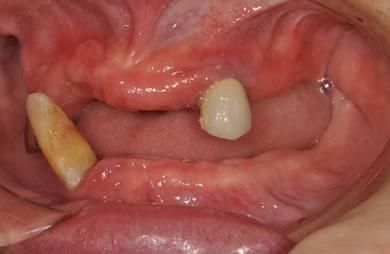

インプラントの症例写真 IMPLANT

骨再生スピードインプラント治療+AGC連結セラミック治療

| 性別/年齢 | 女性 / 57歳 | ||||||||||||||||||||||||||||||||

| 主訴 | 全体的に歯が無いので相談したい。 | ||||||||||||||||||||||||||||||||

| 治療内容 | インプラント12本(サイナスリフト+GBR+抜歯即日スピードインプラント+遊離歯肉移植)、AGCハイブリッドセラミック連結ブリッジ2装置(上顎・下顎)、テンポラリーインプラント2本 | ||||||||||||||||||||||||||||||||